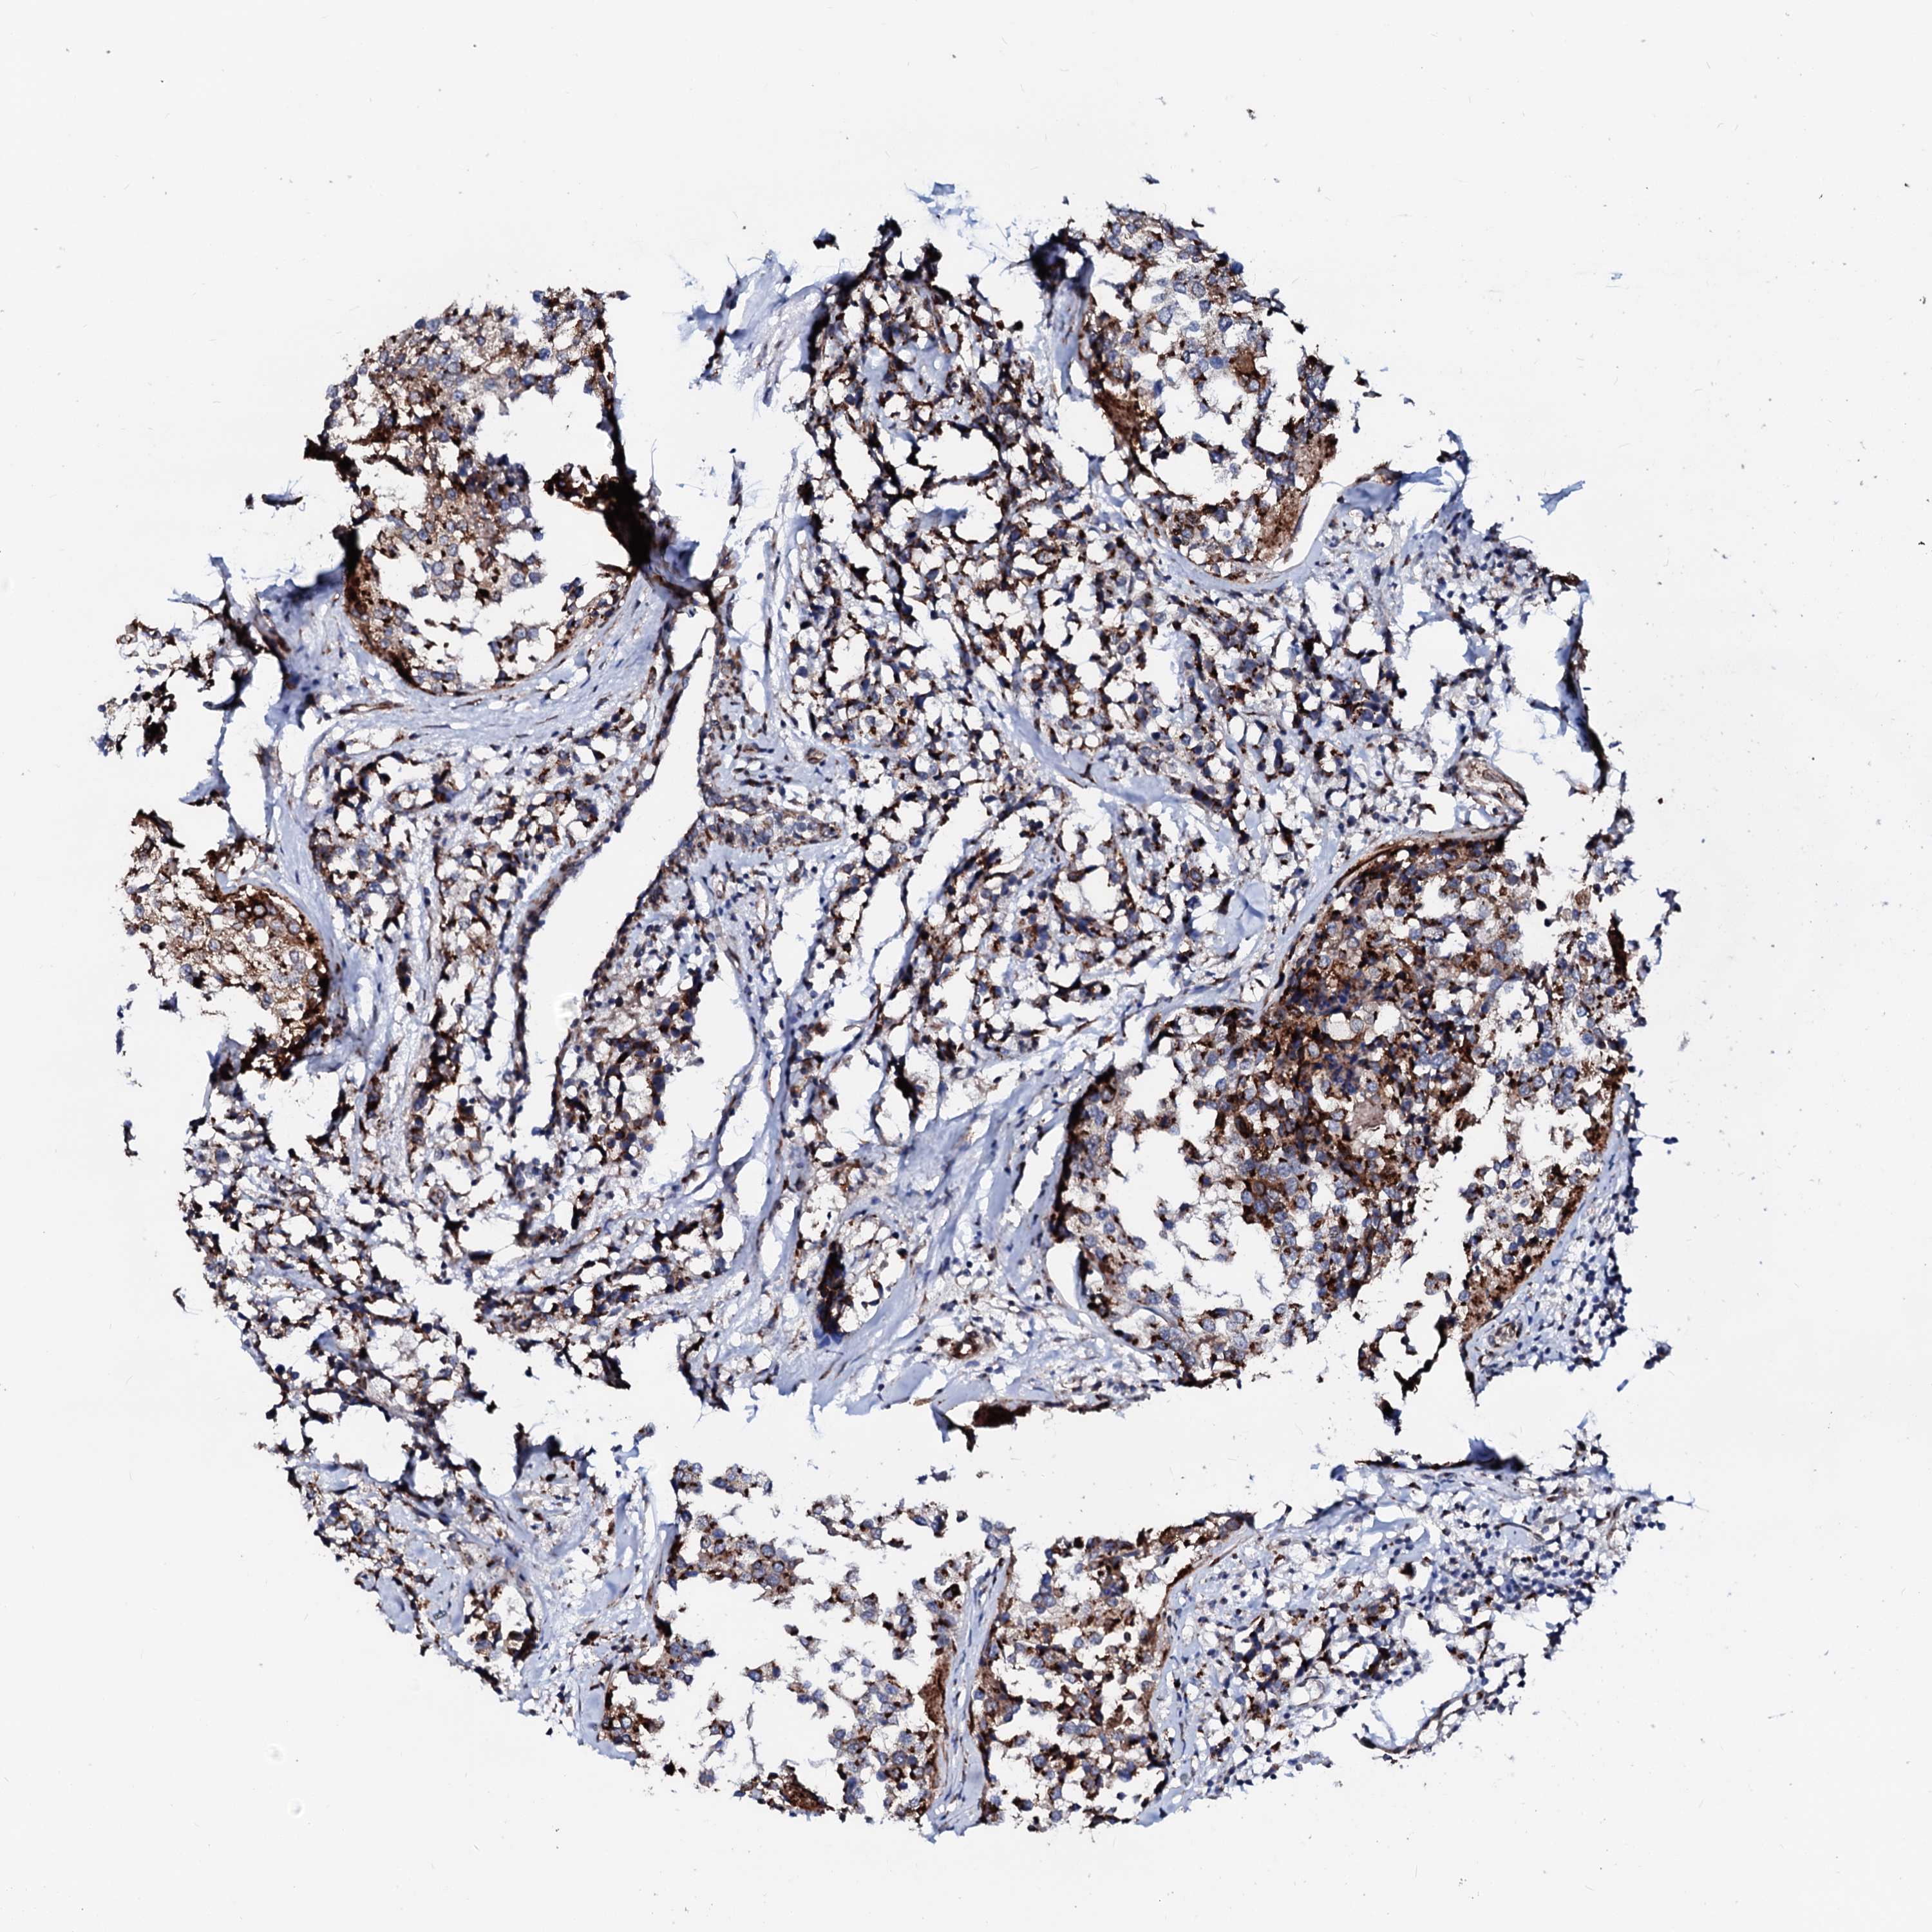

CANCER BREAST CANCER Show tissue menu

BRCA TCGA BRCA VALIDATION PROTEIN EXPRESSION